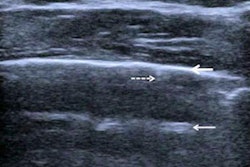

Ground glass on CT (left). Confluent B-lines on ultrasound (right). All images courtesy of Dr. Yale Tung Chen.

Crazy paving, consolidation, and ground glass on CT (left). Irregular pleural line, subpleural consolidation, and confluent B-lines on ultrasound (right).Chen conducted point-of-care ultrasound scans on all patients using a 12-zone protocol. Each zone was assigned a lung ultrasound score (LUS), with higher scores indicating more severe disease.